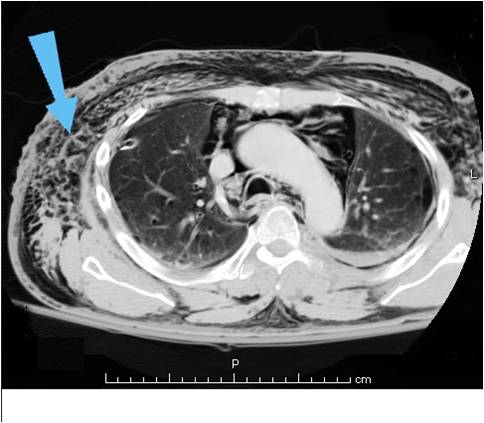

weekly clinical round for undergraduate from 8 to 11 AM during which interpretation of CHEST X rays was done for all cases of cardiothoracic surgery, gived by 2 staf member for 3 months